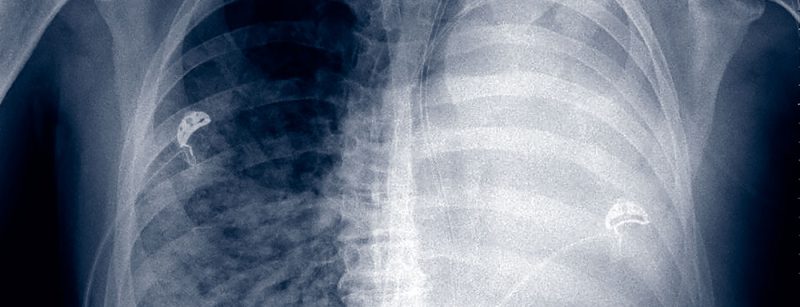

Vermeidung und Behandlung von respiratorischen und kardialen Störungen

Jede Operation kann postoperativ zu Problemen mit dem Kreislauf, dem Herz oder an der Lunge führen. Der Vermeidung solcher Komplikationen und deren Behandlung kommt eine grosse Bedeutung zu, denn sonst...…